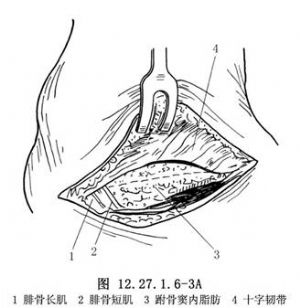

5.2.7.2 2.显露跟距关节

切开深筋膜及十字韧带,在切口后部可见腓骨肌。将皮肤连同皮下组织一起上下牵开,切勿过多游离或过度牵拉,以免皮肤坏死(图12.27.1.6-3A)。切开跗骨窦内脂肪后,再切开并剥离部分骨膜,在伤口深部显露跟距关节(图12.27.1.6-3B)。